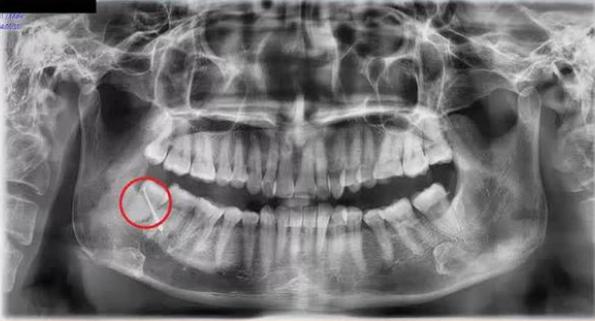

Các bác sĩ chỉ định nhập viện điều trị ngay với chẩn đoán: Áp xe vùng má phải do răng số 48 mọc lệch. Đồng thời, thực hiện phẫu thuật cắt đường dò má và nhổ răng nguyên nhân. Đây là chiếc răng khôn nằm tại vị trí hàm dưới bên phải trên cung hàm của bệnh nhân.

Thông tin từ một bệnh viện đa khoa tại Phú Thọ cho biết, các bác sĩ đã phẫu thuật thành công cho một bệnh nhân bị thủng má do răng khôn mọc lệch lâu ngày mà không biết.

Dây là trường hợp hy hữu, răng khôn mọc lệch đâm thủng má vẫn nghĩ là... mụn. Bệnh nhân tự điều trị tại nhà bằng thuốc tự mua và thuốc nam vì chủ quan nghĩ là mụn bình thường.